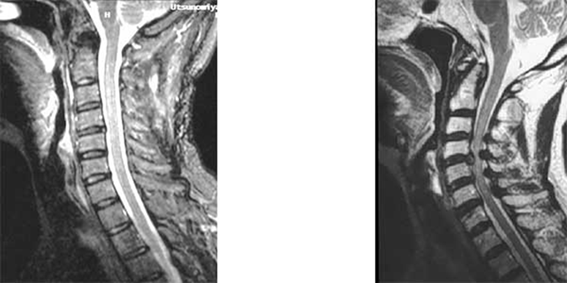

写真は頚椎のMRIです。成人男性の頚椎を横から見たところです。向かって左側が顔、右側が後頭骨です。ほぼ中央を縦に降りてくるのが脊髄です。左の写真では圧迫がありませんが、右の写真では4箇所に圧迫がみられます。